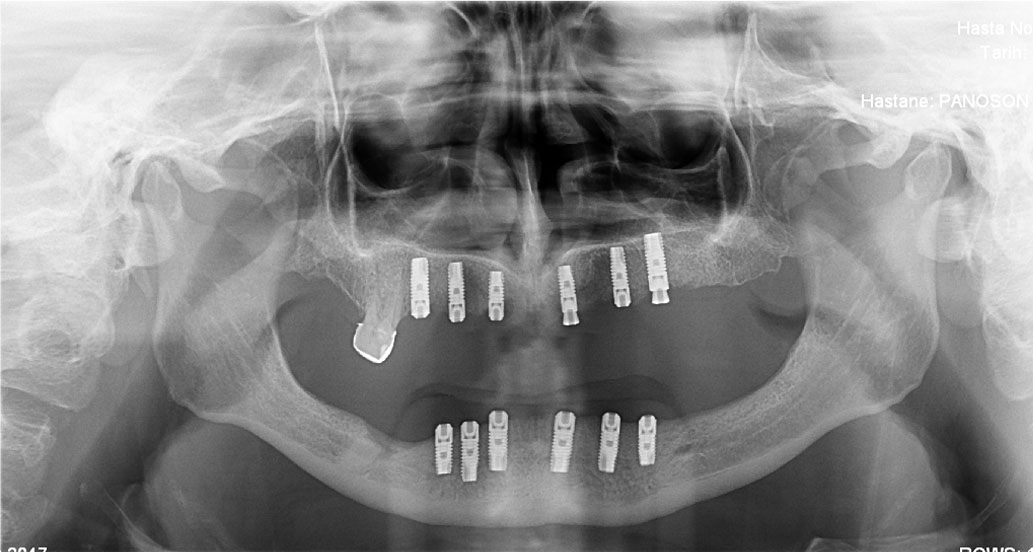

Ýmplant

Oral Diagnoz ve Radyoloji